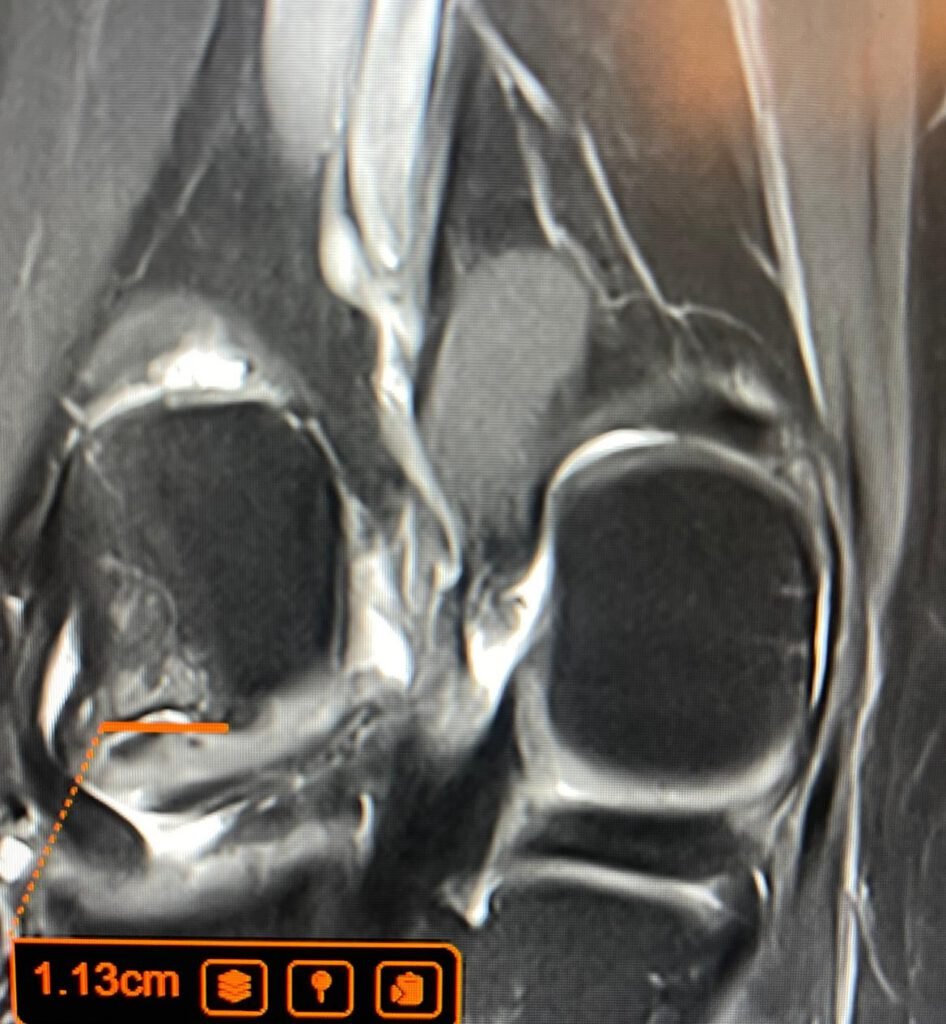

When the patient came to LSRI and underwent an urgent MRI, Dr Prashant Sankaye’s review of the images clearly revealed advanced Osteochondritis Dissecans (OCD) — a condition where a segment of cartilage and underlying bone separates from the joint surface due to insufficient blood supply. Standard X-rays had been reported as normal by his GP. Because standard X-rays cannot reliably detect OCD in its early stages, advanced imaging is the gold standard for assessing this type of condition.